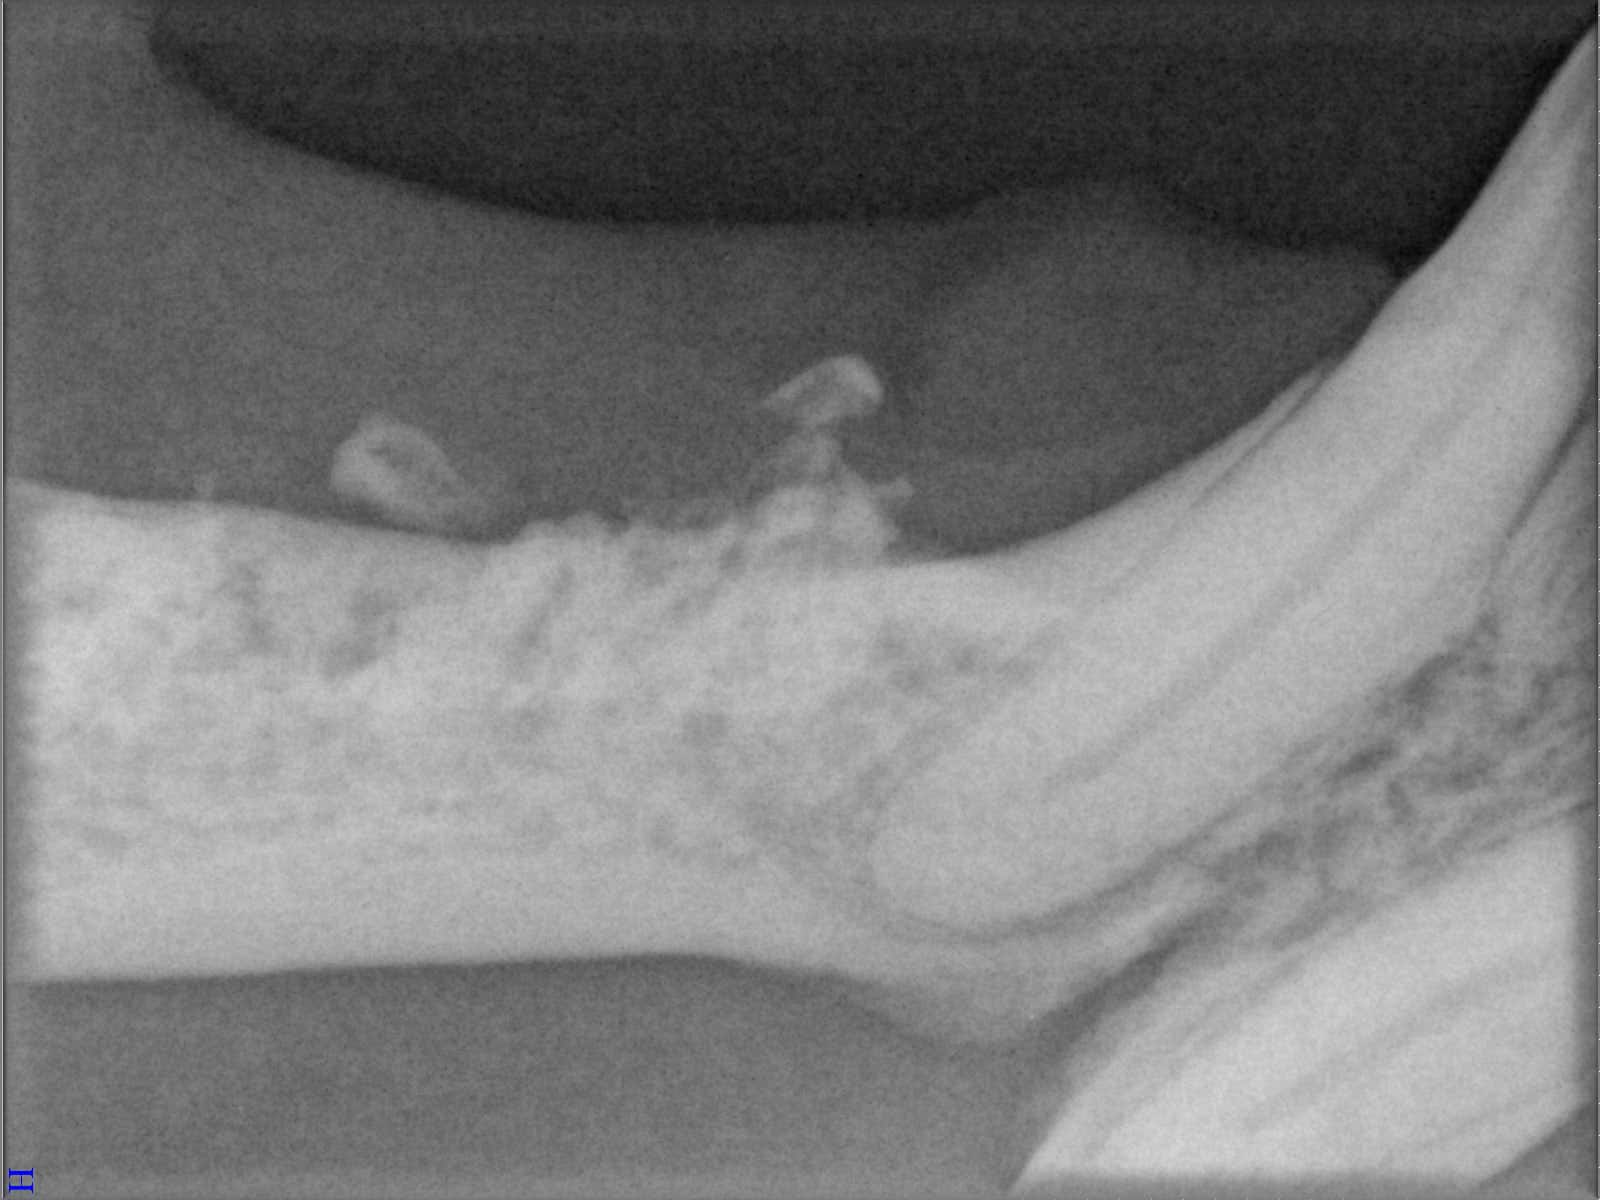

Ein entscheidender Baustein der FORL-Diagnostik ist das dentale Röntgen. Viele Läsionen sind von außen nicht sichtbar und lassen sich ausschließlich mithilfe moderner Röntgentechnik erkennen. In der Hamburger Praxis kommt digitales Dentalröntgen zum Einsatz, das detailreiche Aufnahmen bei geringer Strahlenbelastung ermöglicht. So kann FORL bereits in frühen Stadien diagnostiziert werden.

Das sehen Sie von außen – so sieht es auf den Röntgenbildern aus.

FORL Katze Röntgenbild

Röntgenbilder